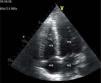

Case reportA 21-year-old man, black, a football player, was admitted via the emergency department with a clinical and laboratory diagnosis suggestive of acute appendicitis. There was no relevant family or personal history. Physical examination showed no abnormalities other than in the abdominal region. He underwent laparoscopic appendectomy under balanced general anesthesia, both of which were uneventful. The patient was extubated at the end of the procedure following reversal of neuromuscular blockade. Immediately after extubation, he developed a setting of respiratory distress, with abundant pink frothy sputum and significant arterial desaturation. Physical examination and chest X-ray revealed the presence of APE (Figure 1). After orotracheal reintubation and connection to a ventilator, the patient was transferred to our unit. Following treatment including high-flow oxygen therapy and administration of intravenous boluses of furosemide and isosorbide dinitrate, he showed rapid improvement and was extubated around four hours later (Figure 2). Other laboratory tests, together with electrocardiographic and echocardiographic assessment (Figures 3 and 4) excluded heart disease. There were no further complications.